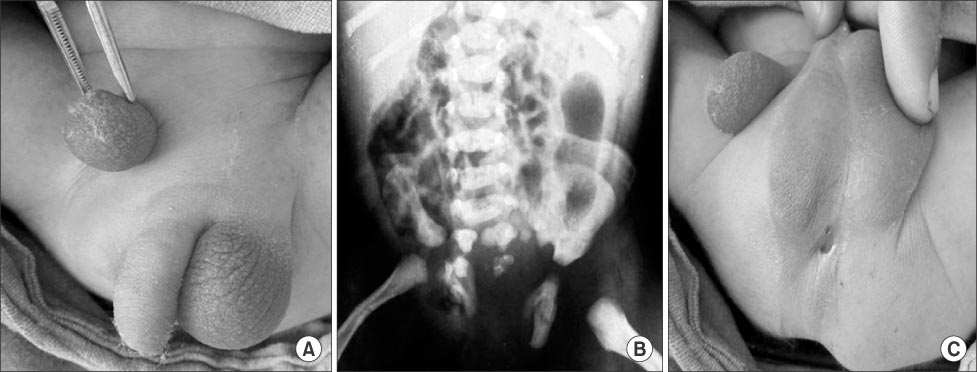

A two-day-old male neonate was admitted with us for ectopic scrotum and imperforate anus. There was no family history of any similar congenital anomaly. Physical examination showed an ectopic scrotum in the right inguinal area. The opposite left side hemiscrotum was normotopic and both testes were located in each hemiscrotum. Scrotal raphe was moderately developed. The phallus was normal in gross. He also had low anorectal malformation in the form of a perineal fistula and a flexion contracture of right knee (arthrogryoposis) and ipsilateral club foot (talipes equino varus) as musculoskeletal anomalies (

Fig. 1).

Plain radiography of the spine revealed hemisacrum and hemipelvis (

Fig. 1). Abdominal sonography showed a normal upper urinary tract.

Fig. 1(A-C) Photographs show ectopic scrotum in the inguinal region with low anorectal malformation with sacral agenesis.